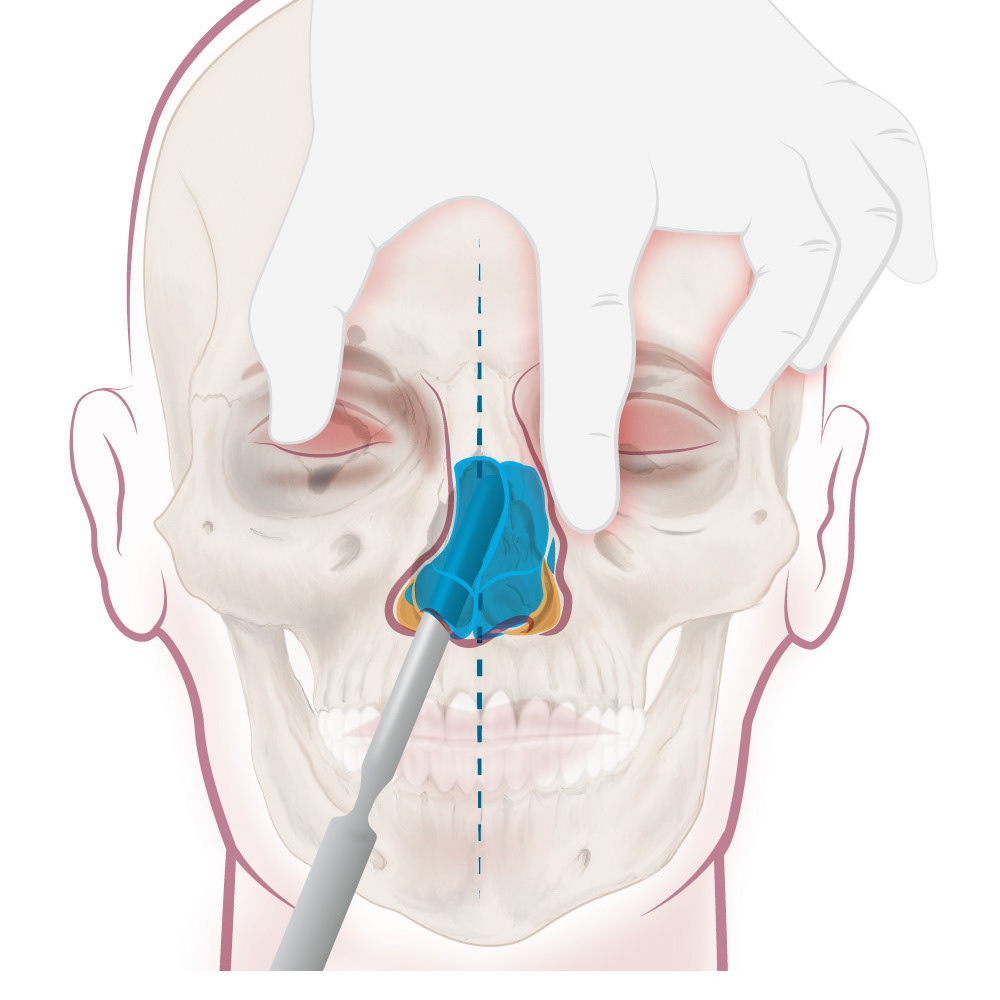

Proceso / Maxilofacial